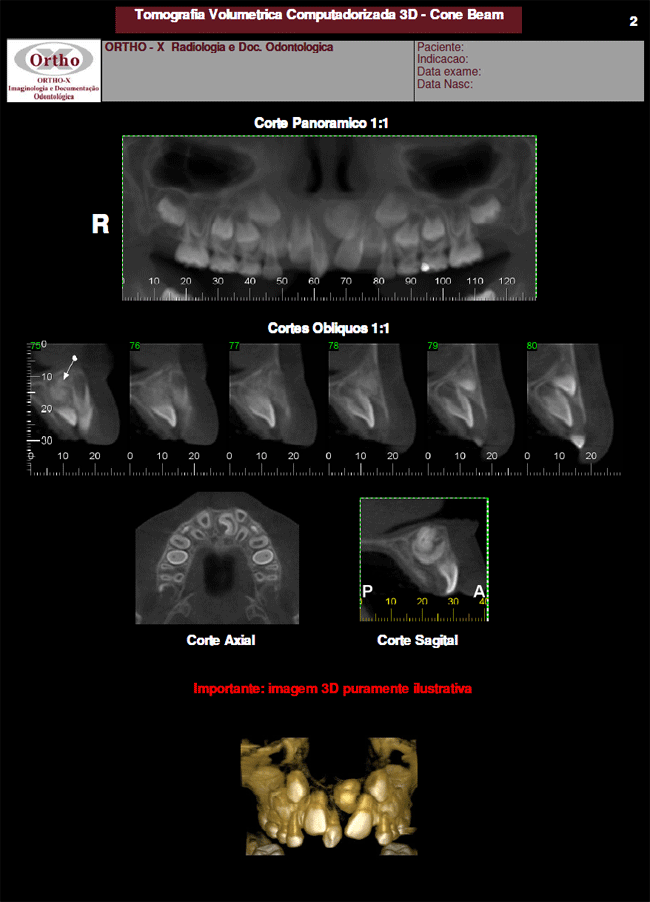

Exames > Tomografia Computadorizada 3D > Exemplo de Exames: Supranumérico

Exemplo de Exames: Supranumérico